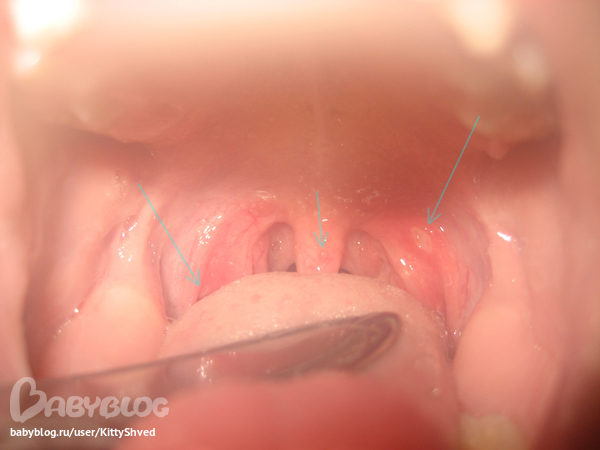

Началось с температуры 37.5-38.Заметили справа на нёбной дужке прыщик с белой головкой, который с течением времени превратился в язвочку, затаем похожее появилось на левой.Температуры уже 4 дня нет.На фото подозрительные места обозначила.Врач была,сказала скорее всего стоматит,но не уверенна.Перестраховалась и назначила антибиотик вместе с традиционным лечением стоматита.Как Вы думаете картина похожа на стоматит, или в этих местах стоматит врят ли возможен?Больше язвкчек в ротике нет - щёки,нёбо,дёсна - всё чисто.Девочке 5лет.

И мне на стоматит похоже

Но я бы антибиотики отсрочила пока....Если стандартное лечение не поможет, только бы тогда их присоединила.